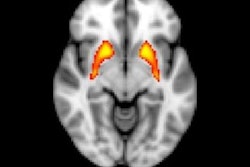

Object memory is more vulnerable than spatial memory in the early stages of brain diseases such as Alzheimer's, the group wrote. By scanning study participants' brains while they underwent fMRI, Reagh and colleagues were able to establish a mechanism within the brain for that deficit in object memory, finding that it was linked to a loss of signaling in the anterolateral entorhinal cortex. The researchers did not find age-related differences in another area of the brain connected to memory, the posteromedial entorhinal cortex, which supports spatial memory function.

The figure shows two different brains aligned to a common template space for comparison. The yellow in the anterolateral entorhinal cortex of the young brain indicates significant activity, something that is absent in the older brain. Courtesy of Zachariah Reagh, PhD.Reagh and colleagues now plan to explore whether this type of fMRI scan could eventually be used as a tool for early diagnosis. They will expand their work to a sample of 150 older adults who will be followed over time, and the subjects will also receive PET scans to track amyloid and tau pathology.